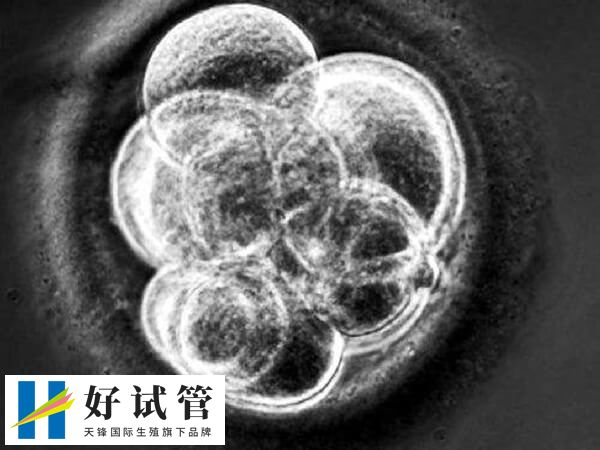

四级胚胎养囊成功率

四级胚胎养囊成功率通常较低,一般在10%左右。这是因为四级胚胎细胞大小严重不均匀、细胞质有严重颗粒现象,且碎片程度≥50%,发育潜能相对较弱。不过,在合适的培养条件下,部分四级胚胎仍有成功养囊的可能。